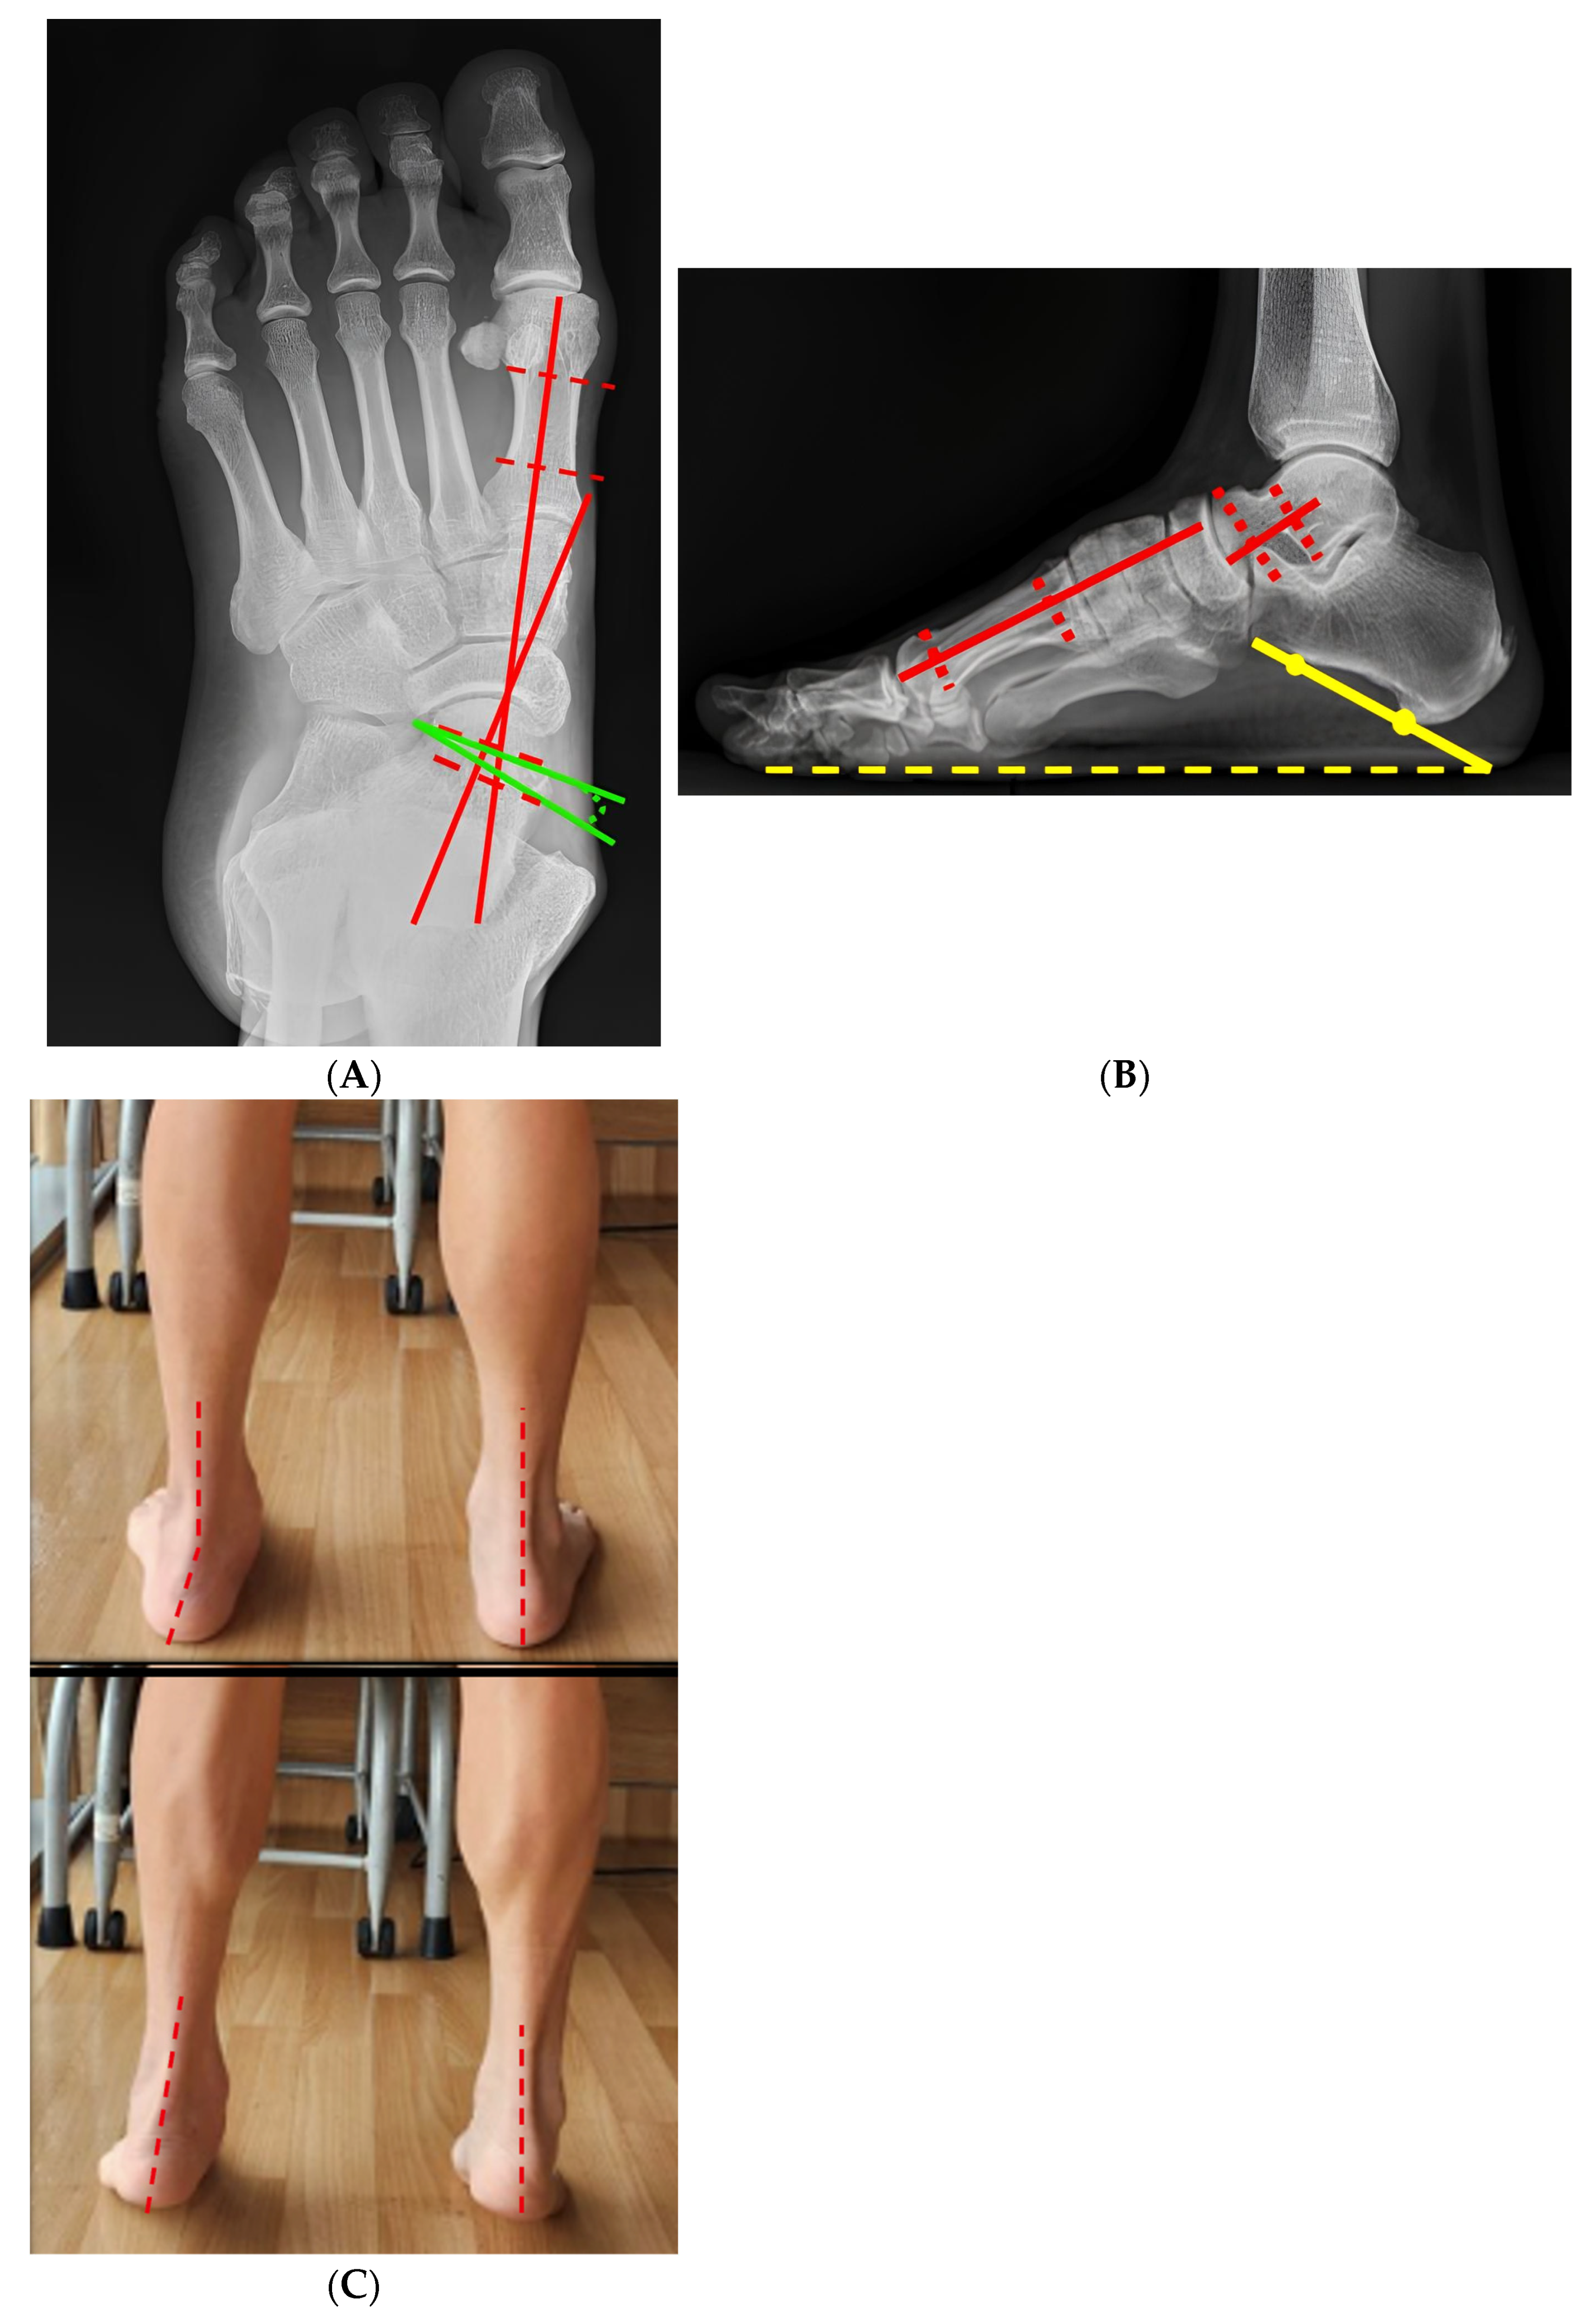

3.6. Representative Case

| Parameter | Preoperative | Postoperative | 24 Months of Follow-Up | p-Value |

|---|---|---|---|---|

| Meary angle (AP, °) | 24.2 ± 7.4 | 9.2 ± 4.1 | 8.6 ± 4.1 | <0.001 |

| Meary angle (Lateral, °) | 9.96 ± 2.3 | 1.92 ± 1.4 | 2.05 ± 1.6 | <0.012 |

| Calcaneal pitch (°) | 10.64 ± 4.87 | 15.78 ± 3.33 | 15.55 ± 4.25 | <0.01 |

| Talonavicular coverage angle (°) | 14.53 ± 6.67 | 3.46 ± 1.56 | 3.58 ± 0.78 | <0.024 |